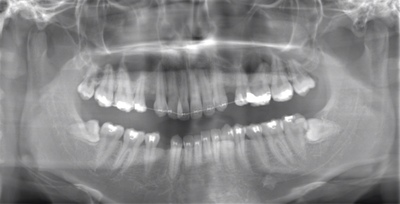

CASE 3

| 年齢・性別 | 20代・男性 |

| 主訴 | 左下親知らず抜きたい |

| 親知らずのはえ方 | 半埋伏 |

| 抜歯期間 | 30分 |

| 抜歯費用 | 約2,500円(保険内) 別途CT撮影で3,000円 |

| 抜歯内容 | 左下の半埋伏親知らず抜歯 |